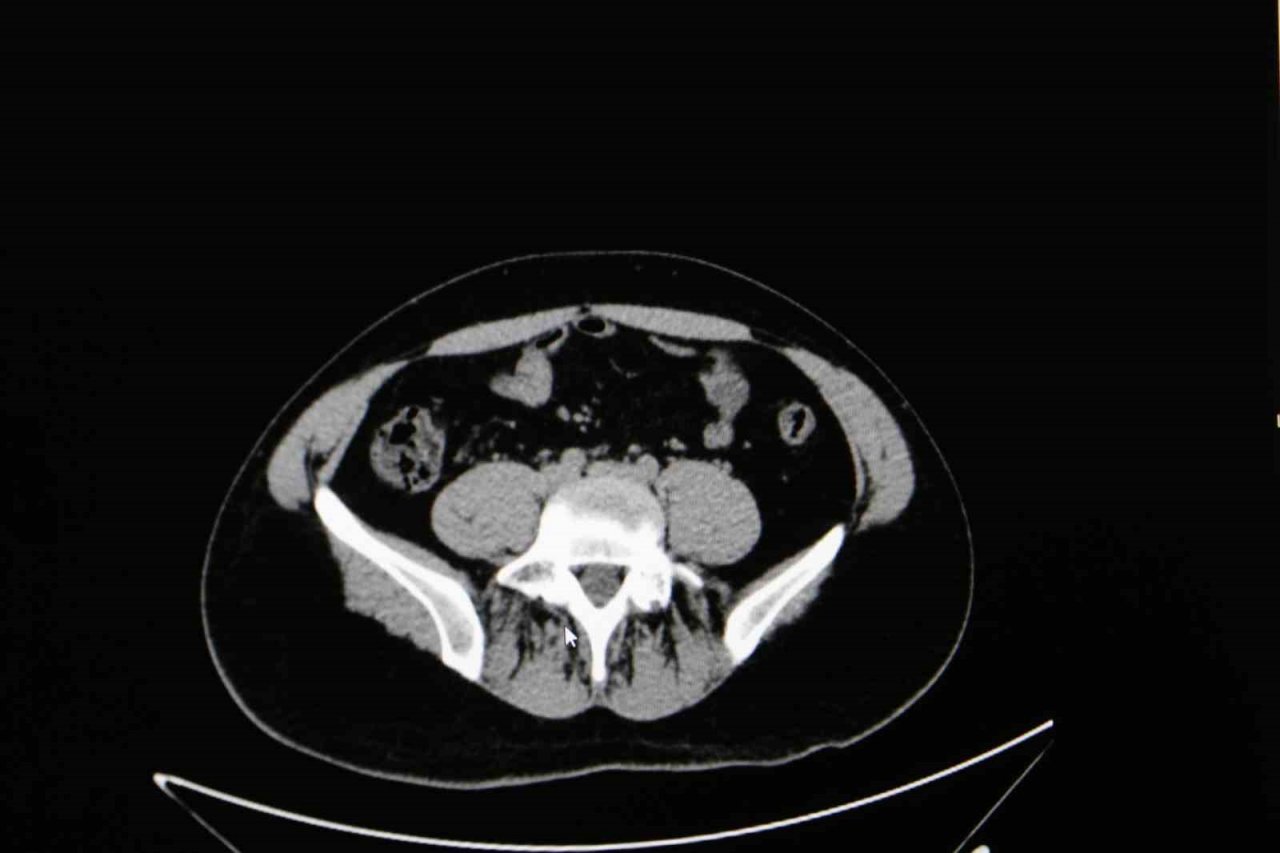

Diyarbakır Dicle Memorial Hastanesi'nde görev yapan Üroloji Uzmanı Op. Dr. Birgi Ercili "Sistit, aslında idrar torbası dediğimiz mesanenin iltihabıdır. Daha çok enfeksiyon sebepleriyle oluşur. Sistin daha çok sebebi idrar yoluna genital bölgeden ulaşan mikroorganizmalardır. Özellikle kadınlarda sistit dediğimiz durum çok fazla görülür. Çünkü kadınlarda üretra dediğimiz idrar yolu, erkeklere göre oldukça kısadır. Vajina ve anüse yakın olduğu için oradan gelen mikroorganizmaların idrar yolu aracılığıyla mesaneye ulaşması daha kolaydır. Kadınların yarısı hayatlarında muhakkak en az bir defa bu hastalığı geçirmektedir" ifadelerine yer verdi.

Sistitin sık görülen belirtilerinden idrar yanması ve az idrar yapma olduğunu ifade eden Ercili, "Sistit geliştiğinde özellikle idrarda yanma, sızı, sık sık ve az idrar yapma, damla damla idrar yapma, kasık ve alt karın bölgesinde ağrı, idrarda kan ve bulanık idrar görülebilir. Bazen de kadınlarda ilişki sonrası ağrı görülebilir. Genital hijyene çok dikkat edilmemesiyle, tuvalet temizliğini arkadan öne doğru yapılmasıyla mikropların idrar yoluna daha hızlı şekilde ulaşabildiğini görmekteyiz. Bunların dışında nemli çamaşırlarla beklemek, sık çamaşır değiştirmemek, az sıvı almak sistite sebep olabilmektedir. İlişki sonrasında da yine idrar yolunda tahriş meydana geldiği için sistit durumlarını görebilmekteyiz" diye konuştu.